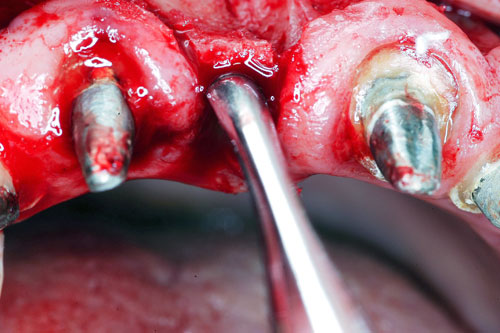

Mientras dichos movimientos ortopédicos se producen (período que supondrá otros seis meses), estudiamos los actos quirúrgicos a realizar en los cuatro implantes que pondremos. De acuerdo al estudio Desatascan realizado observamos tres situaciones diferentes: 1º-El Primer Molar Inferior Izquierdo, lo instalamos mediante Cirugía Minimamente Invasiva , con la aplicación de una Férula Quirúrgica Obtenida de los datos del scanner tratados con un programa de CMI (Cirugía Minimamente Invasiva), previa prueba en un modelo estereolitográfico, ya que la altura ósea era apenas de 9 mm. 2º- El Primer Molar Superior Derecho, se implantará mediante una ligera Elevación Atraumática (Trans alveolar) de Seno una vez logrado el espacio mesio distal necesario. 3º- El Incisivo Central Superior Derecho ausente, cuenta con un sustrato óseo prácticamente inexistente. El espesor de la tabla era de menos de 2 mm. Los caminos posibles a seguir para contar con una Rehabilitación de piezas independientes son dos: Optamos por esta segunda opción por ser menos cruenta y no necesitar de una zona dadora. Técnica esta que pondremos en práctica en dos etapas diferidas: 1º-Incisión horizontal palatinizada, incisiones peri rodetes gingivales e incisiones de descarga. Dilatación que comenzamos con dos incisiones de descarga sobre la cortical vestibular realizadas con disco. y el comienzo de la dilatación propiamente dicha mediante una hoja de bisturí, para luego seguir con un periostótomo . Recién después de alcanzada una cierta separación de la cortical vestibular de la palatina, empezamos con los dilatadores roscados. En este punto podríamos haber utilizado sin riesgos un Implante de 3,8 mm de diámetro, pero a fin de mejorar la estética del pilar emergente decidimos rellenar con material osteoconductor y osteoinductor (BiOss) y cubrir mediante membrana reabsorvible ( Bio Guide). 2º-Implantación seis meses después. Mientras se van cumpliendo los tiempos antes mencionados, y comprobamos reiteradamente la funcionalidad de la oclusión con los provisorios, tomamos impresiones definitivas y construimos primero el maxilar inferior, para definir en primer término la porción inferior de la Guía Anterior., y a nivel posterior Curvas y Microplanos. Para luego realizar los cuadrantes premolar- molar del superior: La espera de la regeneración ósea y sus tiempos pertinentes, más la espera de los tiempos de la implantación, nos obligaron a modificar las etapas del protocolo D.AT.O de manera de mantener la –D- mediante el sector superior de la GA. en provisorios, mientras fuimos resolviendo en forma definitiva los demás sectores. Ya pasados los meses necesarios para recrear un hueso adecuado en el área del Incisivo Superior Derecho, procedemos a resolver la implantación de dicha zona, observando que todo el esfuerzo dedicado al mismo había sido inútil, ya que la formación de hueso se produjo minimamente. Cuatro meses después tomamos impresiones del sector Antero Superior de la Guía Anterior, incluyendo el arrastre de un transfer . Seguimos modelando la encía con un nuevo juego de provisorios. Y se construye entonces el sector superior de la Guía Anterior. Se efectúa un control radiográfico a los 6 meses. Se ha intentado mostrar en esta Rehabilitación, que a pesar de las distintas circunstancias de cada paciente, siempre debemos tener en cuenta la necesidad de ejercer la DESOCLUSIÓN del caso como prioridad número uno, para luego perseguir la ALINEACIÓN TRIDIMENSIONAL de las arcadas y obtener así una OCLUSIÓN equilibrada. D.AT.O. ES EL PROTOCOLO QUE DEBEMOS SEGUIR EN TODA REHABILITACIÓN. BIBLIOGRAFÍA 1)William Mc Horris,B.S.,D.D.S. Oclusión. Con especial énfasis sobre :El rol funcional y parafuncional de los dientes anteriores. 2)Von Spee , Craff(Anatomista alemán, describió la curva de compensación de la articulación de molares y premolares).CURVA DE SPEE 1.89 3)Stuart,D.”Some aspects of the inervation teeth.”Procedings of Royal Society of Medicine.20:1675,19274)Muhleman,H. y Savdir,S”Tooth movility-its causes and significance”Journal of Periodontology ,36:153,Marzo ,Abril,1965. 4)Muhleman,H. Y Savdir,S”Toothmovility its causes and significance” Journal of Periodontology,36:153,marzo,abril,1965. 5-Oclusión y Diagnóstico en Rehabilitación Oral. 6-Anatomia Odontológica. 7-A contribution to the study of the movementes of the mandible. 8-Celenza F.W, Nadeskin J.F.,Oclusión.Situación actual. 9-D´Amico 10-Dawson P.E. 11-Huffman –Regenos. 12-Hobo S.-Takayama H.A. 13-Lucia V.O 14-Mc Horris. 15-Mc Horris. 16-Stuart C. 17-Vartan Veshnilian 18-Alvarez Cantoni H. AUTOR:Ratificación del Protocolo en Rehabilitación Bucal a pesar de las incidencias propias de cada caso clínico. A propósito de un caso.

Verificamos también el escaso ancho crestal, lo que nos obliga a utilizar dilatadores roscados y un osteótomo para elevar inicialmente la membrana de Schneider.

Elevación de membrana mediante periostótomo

Elevación de membrana mediante periostótomo